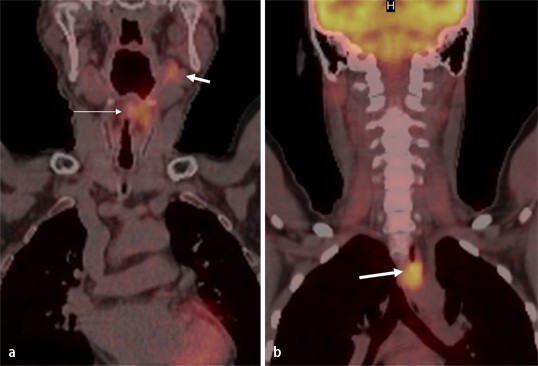

Lesions Revealed By 18 F Fdg Pet Ct In Sapho Syndrome White Arrows Download Scientific Diagram